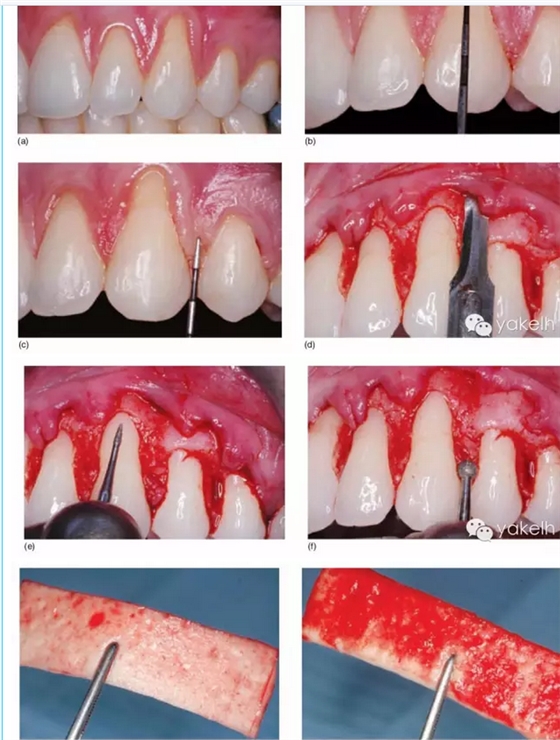

¤¤之后將組織瓣無張力地冠向復位,覆蓋在去上皮的齦緣上。雙側進行懸吊縫合,腭側打結。在冠向復位瓣縫合前或縫合后,使用注射器將釉基質(zhì)衍生物凝膠覆蓋在牙根面上(圖5.13a~f)。

圖5.13 (a)Ⅰ/Ⅱ類牙齦退縮。(b)沿牙間乳頭及齦緣做溝內(nèi)切口,翻全厚瓣和半厚瓣。(c)去除余留齦乳頭的上皮組織,平整牙根后,以PrefGel™做根面處理。(d)經(jīng)沖洗和干燥后,根面注入Emdogain®凝膠。(e)將組織瓣進行冠向復位,懸吊縫合固定。(f)術后1年,牙齦退縮位點被完全覆蓋。

¤¤若使用脫細胞真皮基質(zhì),組織瓣瓣的剝離方法與前述相同。在口外用#15刀片將干燥的脫細胞真皮基質(zhì)移植物切割成所需大小,然后在生理鹽水溶液中浸泡15分鐘潤濕移植物。之后將潤濕后柔軟的膜進行精確塑形調(diào)整,充分貼合術區(qū)、完全覆蓋缺損。將移植物放置于釉牙骨質(zhì)界,其上緣及側緣越過缺損區(qū)牙槽嵴根方缺損至少0.7~1.0mm。放置時,脫細胞真皮基質(zhì)的基底面(帶小凹陷的表面)貼合骨組織和根面,而結締組織或真皮層面則貼合組織瓣(圖5.14a~k)。

圖5.14 (a)使用Emdogain®和AlloDerm®治療Ⅰ/Ⅱ類牙齦退縮。(b,c)頰側牙齦退縮深度,在鄰牙牙齦乳頭做標記,從尖端到基底。(d)分離全厚瓣和半厚瓣,以增加組織瓣的的活動度。(e)用細金剛砂車針進行根面平整,減少根面凸度,注意平整時勿加壓。(f)用金剛砂球鉆去除齦乳頭上皮。(g)將AlloDerm®浸泡于生理鹽水中潤濕后取出,基底面與血液接觸不吸收血液。(h)真皮面可吸收血液,真皮面應貼合組織瓣。(i)AlloDerm®膜覆蓋于齦退縮根面上。(j)AlloDerm®底部注入Emdogain®凝膠,然后將組織瓣冠向復位,縫合固定。(k)術后1年所有牙齦退縮位點根面完全被牙齦覆蓋,獲得滿意的紅色美學效果。GML,齦緣水平;MTC,邊緣組織輪廓;STT,軟組織質(zhì)地;MGJ,膜齦聯(lián)合。